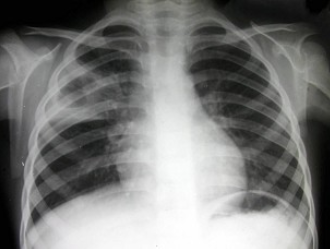

男,69岁,胸闷气逼多年,近来咳嗽,无胸痛、无痰中带血,X线检查如图,最可能的诊断是()

A.慢支肺气肿、右上肺肿瘤

B.慢支肺气肿、右上肺炎性假瘤

C.慢支肺气肿、右上肺结核瘤

D.慢支肺气肿、肺转移瘤

E.慢支肺气肿、结节病

点击查看答案